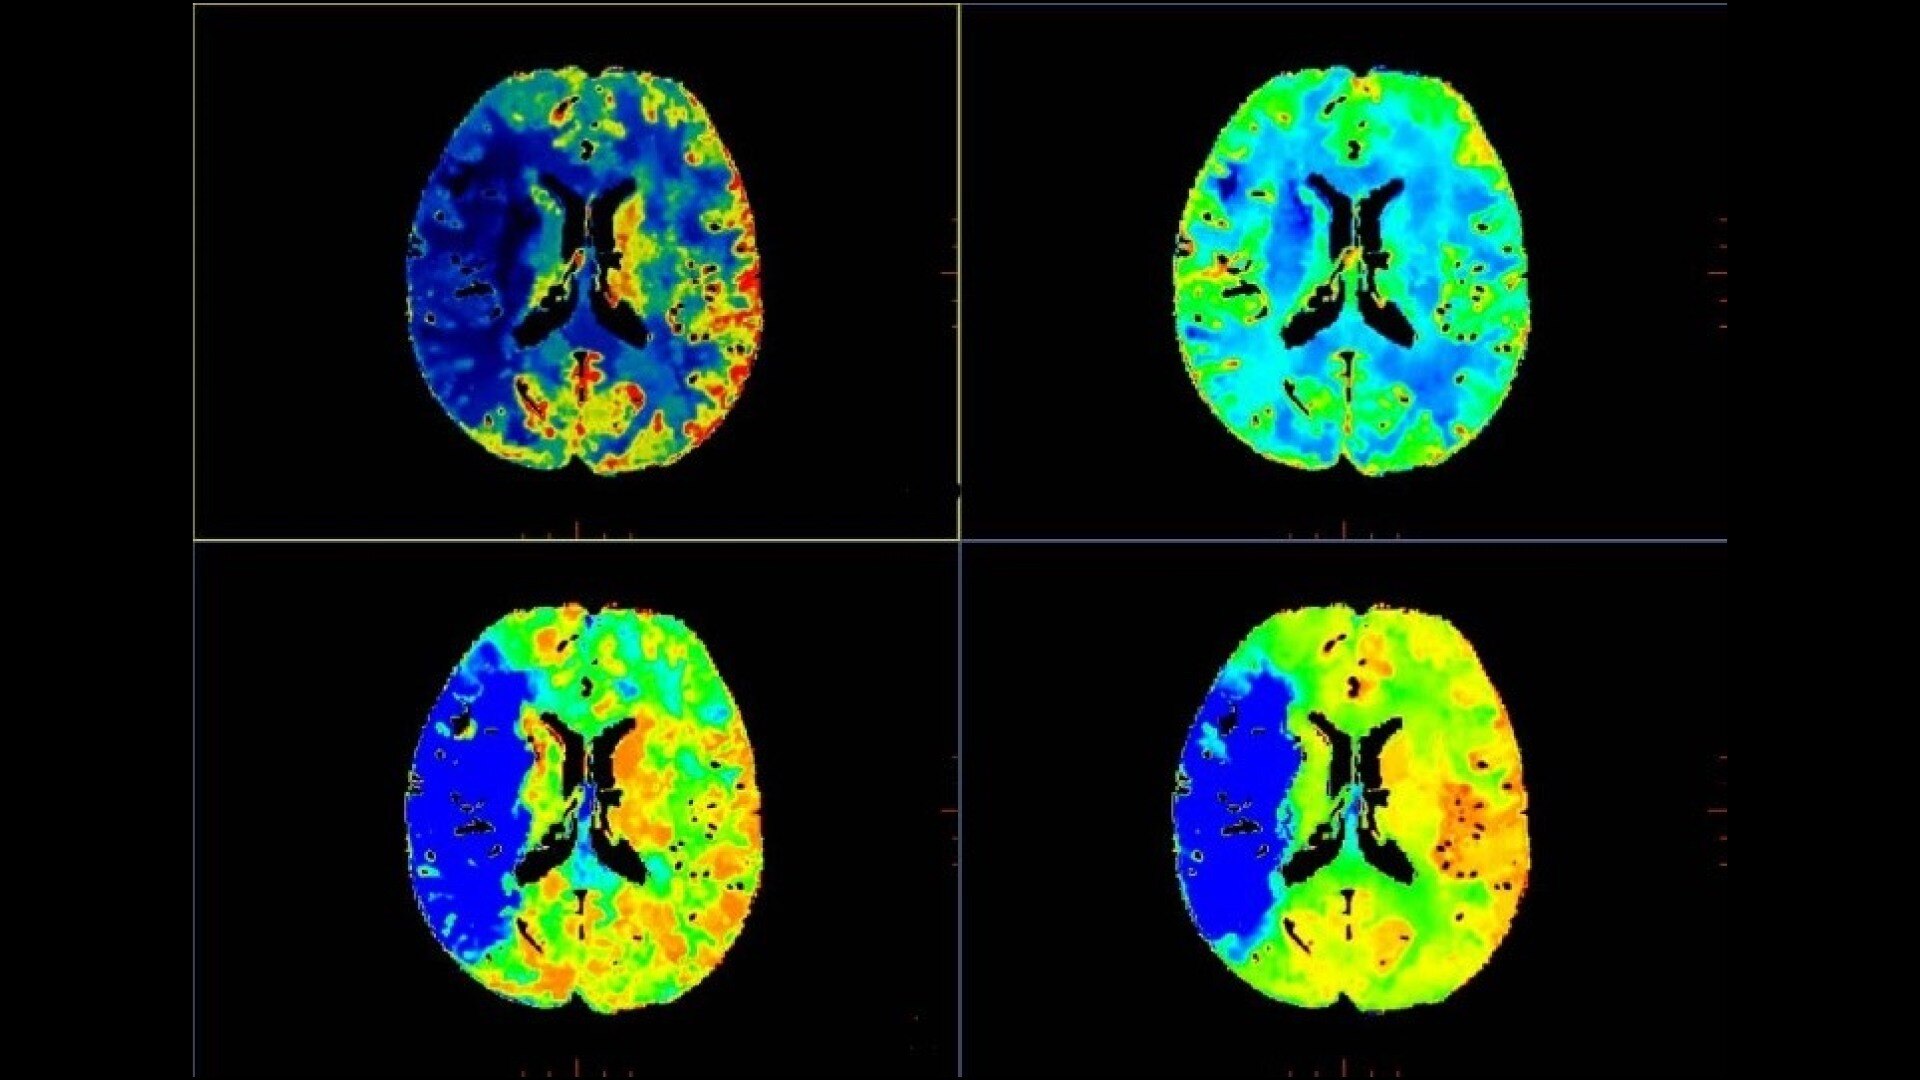

• Automated generation of all functional maps: Blood Flow, Blood Volume, Mean Transit Time, and Transit Time to IRF Peak (Tmax)

• Automatically define the symmetry plane to be used for mirroring ROIs and relative thresholds